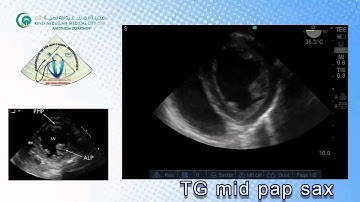

078 Basic View TEE KAMC